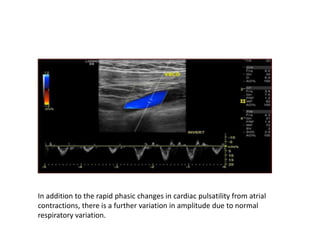

In addition to the rapid phasic changes in cardiac pulsatility from atrial

contractions, there is a further variation in amplitude due to normal

respiratory variation.